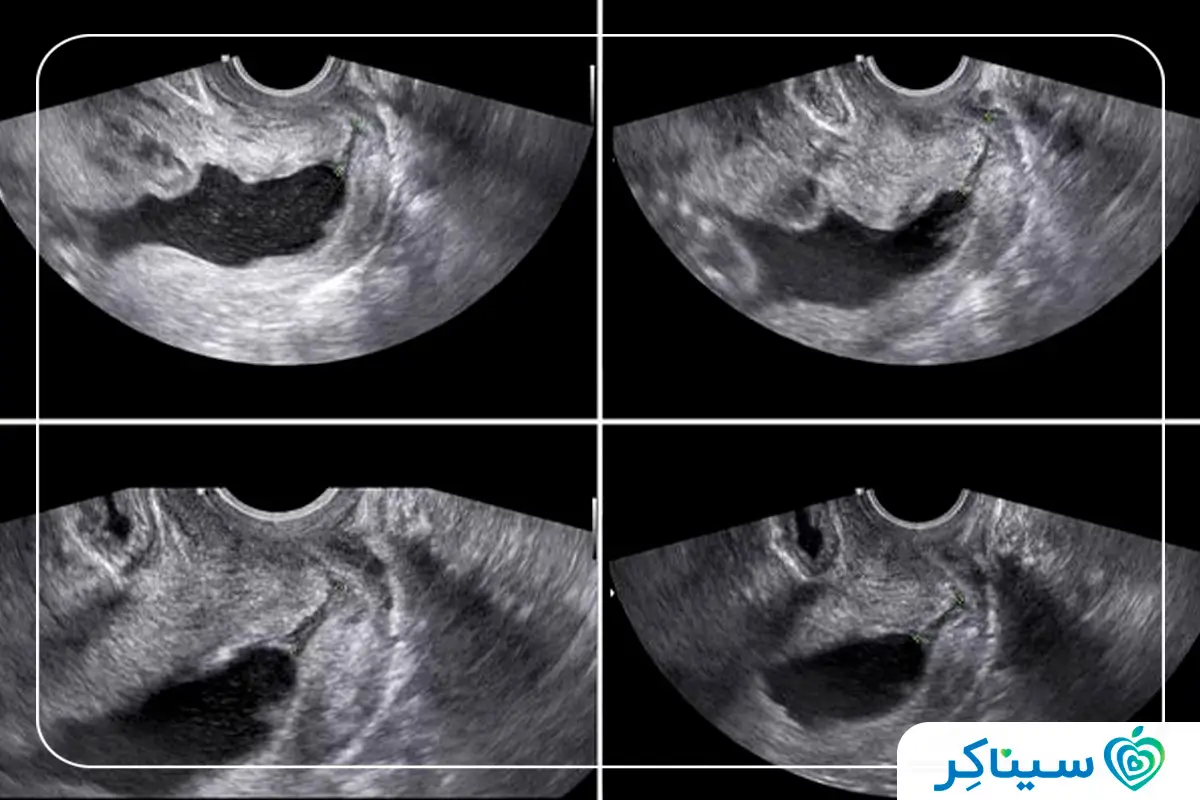

سونوگرافی در هفته هجدهم بارداری

یکی از اقداماتی که در هفته هجدهم بارداری برای بررسی وضعیت جنین انجام میشود سونوگرافی بوده که معمولاً پزشکان در هفته ۱۸ تا ۲۰ بارداری انجام این سونوگرافی را توصیه میکنند.

در این سونوگرافی اندازه جنین مورد بررسی قرار میگیرد و مواردی مثل ویژگیهای فیزیکی، وضعیت قلب، وضعیت مغز، وضعیت ستون فقرات و کلیهها نیز در این سونوگرافی ارزیابی خواهند شد. از طرف دیگر همانطور که اشاره کردیم جنسیت جنین هم در این هفته به طور قطعی مشخص میشود. اگر طی روند این سونوگرافی پزشک مشکل خاصی را مشاهده کند میتواند آزمایشهای تکمیلی را هم تجویز کند.

سونوگرافی هفته هجدهم با عنوانهای مختلف مثل سونوگرافی ساختاری، سونوگرافی سه ماهه دوم بارداری، سونوگرافی سطح ۲ یا بررسی آناتومی جنین شناخته میشود. در این سونوگرافی تمام اعضای بدن جنین بررسی خواهند شد و علاوه بر آن بند ناف، جفت و مایع آمنیوتیک هم در این سونوگرافی اندازهگیری میشوند که از اهمیت بسیار بالایی برخوردار هستند.

عکس سونوگرافی جنین دختر در ۱۸ هفتگی